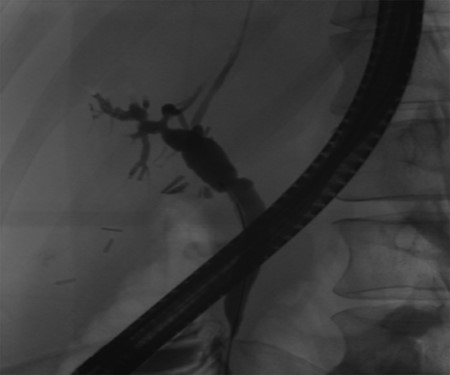

Pre-operative ERCP demonstrating compression of the common hepatic duct.

A 35-year-old female with a medical history significant for acute biliary pancreatitis status post laparoscopic cholecystectomy, presented to the surgery clinic as a new consult for a large cystic liver mass with increasing abdominal pain for 2 weeks. Patient reported suffering from severe pain in right chest, shoulder and diffuse abdominally that worsened with standing. Patient complained of inability to inspire due to pain and a 10-pound weight gain over 2 months. She confirmed decreased appetite especially with solids, nausea and emesis, alternating constipation and diarrhea, bruising, and pruritus at night. Computed tomography (CT) scan demonstrated a peripherally septated 10 x 7 cm cystic mass in the liver with intrahepatic biliary dilation (Fig. 1). The patient was referred for endoscopic retrograde cholangiopancreatography (ERCP) to establish preoperative biliary anatomy and was found to have moderate compression of the common hepatic duct managed with a right hepatic biliary endoprosthesis (Fig. 2); no obvious communication of the biliary tree with the cystic lesion was seen. Patient symptoms persisted despite optimizing with a protein-rich liquid diet; thus, the decision was made to proceed with the surgical plan for an open partial central hepatectomy. The patient was taken to the operative theater. After induction of general anesthetic, an upper midline incision was made. Inspection of the abdomen and liver showed no metastatic lesions grossly or with ultrasonographic imaging. The cyst was visible upon entry into the abdomen with no solid component to the mass in proximity to the cystic neoplasm. The second portion of the duodenum was adherent to the cyst with inflammatory adhesions and was quite boggy. A partial central hepatectomy was performed; a 3 mm biliary duct was found communicating to the cyst only with no drainage to the minimal liver parenchyma that was removed (Fig. 3). The cyst was resected en-bloc and was sent for permanent section (Fig. 4), which diagnosed the tumor as a low-grade mucinous cystic neoplasm measuring 8.5 × 7.2 × 6.4 cm. Microscopy revealed a smooth-walled, multiloculated cyst filled with a yellow-golden, semi-transparent and mucinous fluid (Fig. 5a–c). The cyst was lined by a mucinous epithelium with ovarian-type stroma. No high-grade dysplasia or malignancy was identified. The postoperative course was uneventful, and the patient was discharged on postoperative day 6. At the 4-week postoperative visit, the patient was healing well with some incisional soreness; patient was seen for removal of her biliary endoprosthesis, and ERCP found left sided intrahepatic duct biliary dilatation including a small biliary fistula from the left system (Fig. 6) with the appearance of torque on the extrahepatic biliary tree. A biliary endoprosthesis was left in place, and the patient returned for repeat ERCP 4 weeks later with resolution of all findings (Fig. 7). At present, patient remains alive with no signs of recurrence.